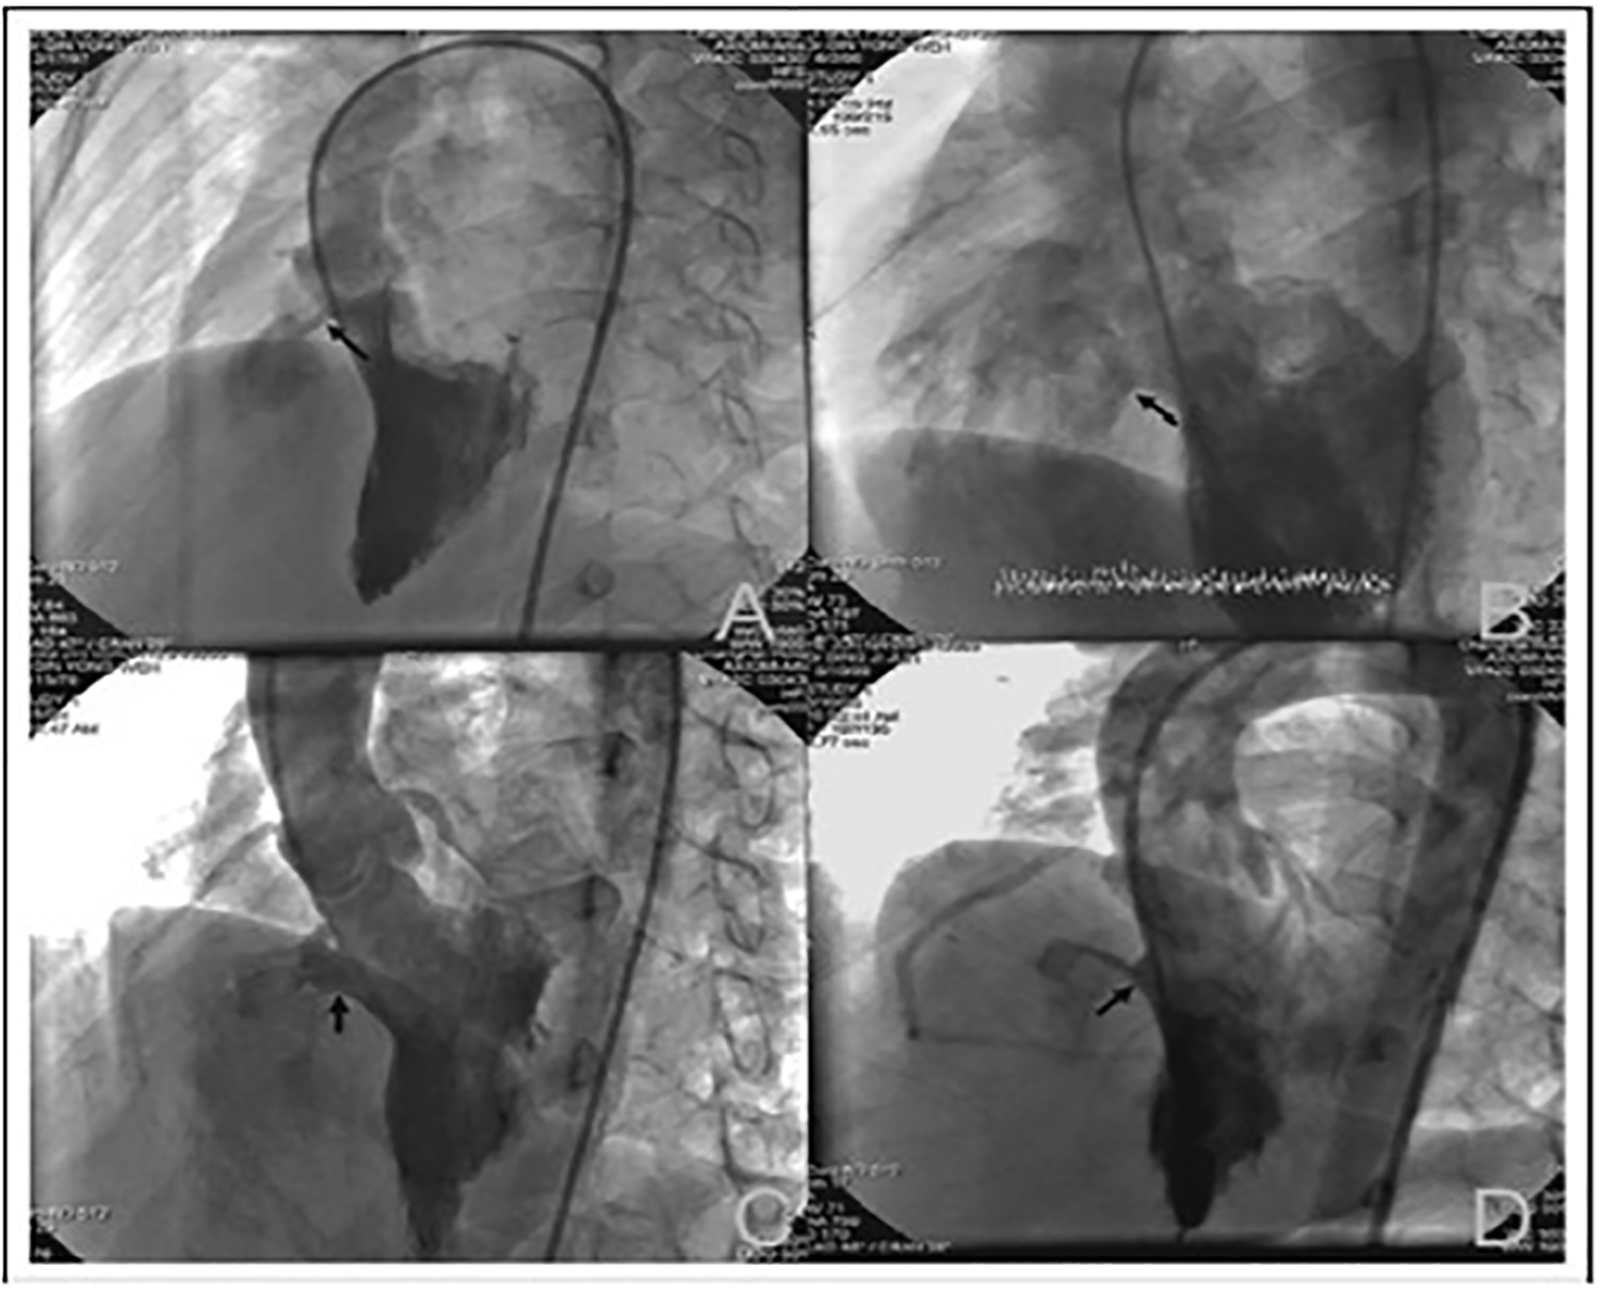

The closure procedure was performed under fluoroscopic and transthoracic echocardiographic guidance. General anesthesia or local anesthesia was used based on patient age and cooperation. The femoral artery and vein were accessed using 4–6F sheaths. After initial heparin administration to maintain activated clotting time >200 s, left ventriculography was performed in a left anterior oblique (40–60°) and cranial (20°) projection to assess the VSD's size, morphology, and its relation to the aortic valve. A 0.035-inch hydrophilic guidewire was advanced through the defect to establish an arteriovenous loop. The double-disc occluder was delivered via a catheter using a kissing-wire technique and deployed under fluoroscopic and echocardiographic monitoring to ensure appropriate positioning and exclusion of residual shunting (8–10). Final assessments included color Doppler imaging and ventriculography to confirm device placement and the absence of significant complications (Figure 1).

Figure 1

Images of different morphological types of perimembranous ventricular septal defects (VSD) observed on left ventriculography: (A) tubular VSD; (B) window-like VSD; (C) VSD with membranous septal aneurysm; (D) funnel-shaped VSD.